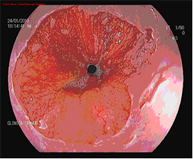

El diagnòstic es porta a terme mitjançant endoscopis d'alta resolució amb magnificació (augment de la imatge), i utilitza tècniques de cromoendoscòpia afegida, realitzades per endoscopistes especialistes en el diagnòstic precoç de les lesiones precanceroses, i la realització de biòpsies que posteriorment són analitzades.

Mucosectomia endoscòpica

La mucosectomia consisteix en la resecció per via endoscòpica d'una secció de la mucosa i submucosa (en aquest cas esofàgica). Està indicada sempre que a l'endoscòpia diagnòstica s'apreciïn lesions sobreelevades a l'esòfag de Barrett.